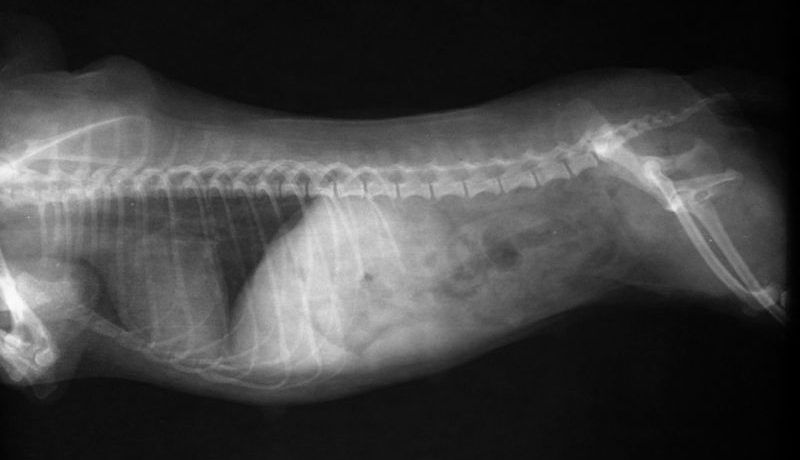

Radiography (X-rays) will allow your vet to visually examine your dog’s chest and abdomen to assess for evidence of heart disease, to check for abnormal accumulation of fluid and identify tumours.